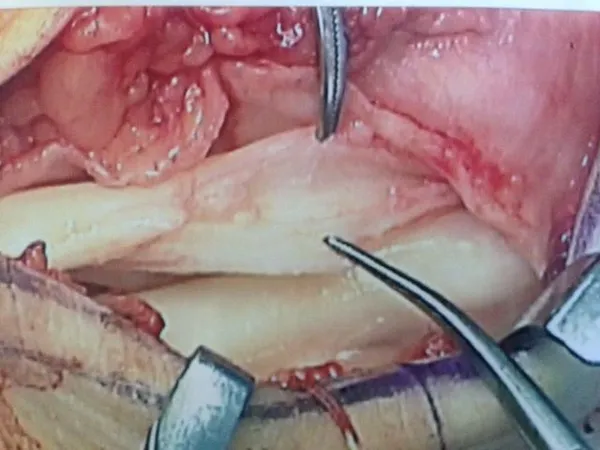

Peroneus Brevis Split Tear with Surgical Repair and Removal of Torn Tendon Portion. (below)

Partial Tear Peroneus Brevis Tendon. (below)

Removal of Torn portion and debulking of tendon. (below)